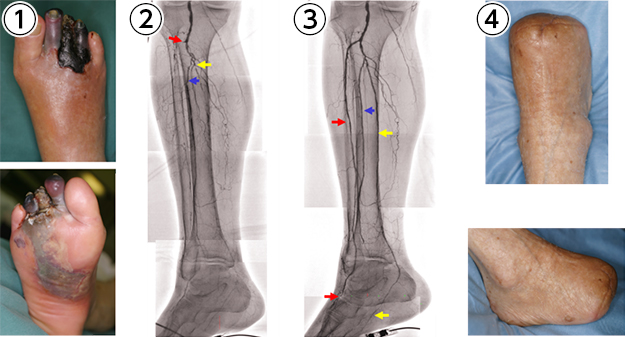

糖尿病性壊疽

傷が治るために必要な血液の流れを良くする治療

①透析患者様に糖尿病性足壊疽が生じました。そのため、感染した壊死組織を切除しました。

②血管造影写真で、膝下の3本の動脈に閉塞が確認された(赤・青・黄矢印の先端部)ので循環器内科でカテーテル治療を行いました。

③3本の動脈すべてで血流が改善されました。

④かかとを残す手術で治癒しました。

傷の背景にある機能障害の回復

①虚血を合併した糖尿病性右足壊疽を生じた患者様は、左下腿をすでに他院で切断されていました(②の*)。

②血管外科で膝の裏と足の甲の間にバイパス手術を行い、血流を改善しました(赤矢印がバイパス血管)。

③かかとの壊疽を切除後に背部の筋肉と皮膚を移植しました。移植した背部の組織の動脈(②青矢印)はバイパス血管(②赤矢印)に顕微鏡を使って吻合しました。右1,4,5趾の糖尿病性壊疽は切断しました。

④右下肢の救肢手術後は、リハビリテーションに努めました。

⑤手術後7年経ちましたが、創傷の再発はありません。